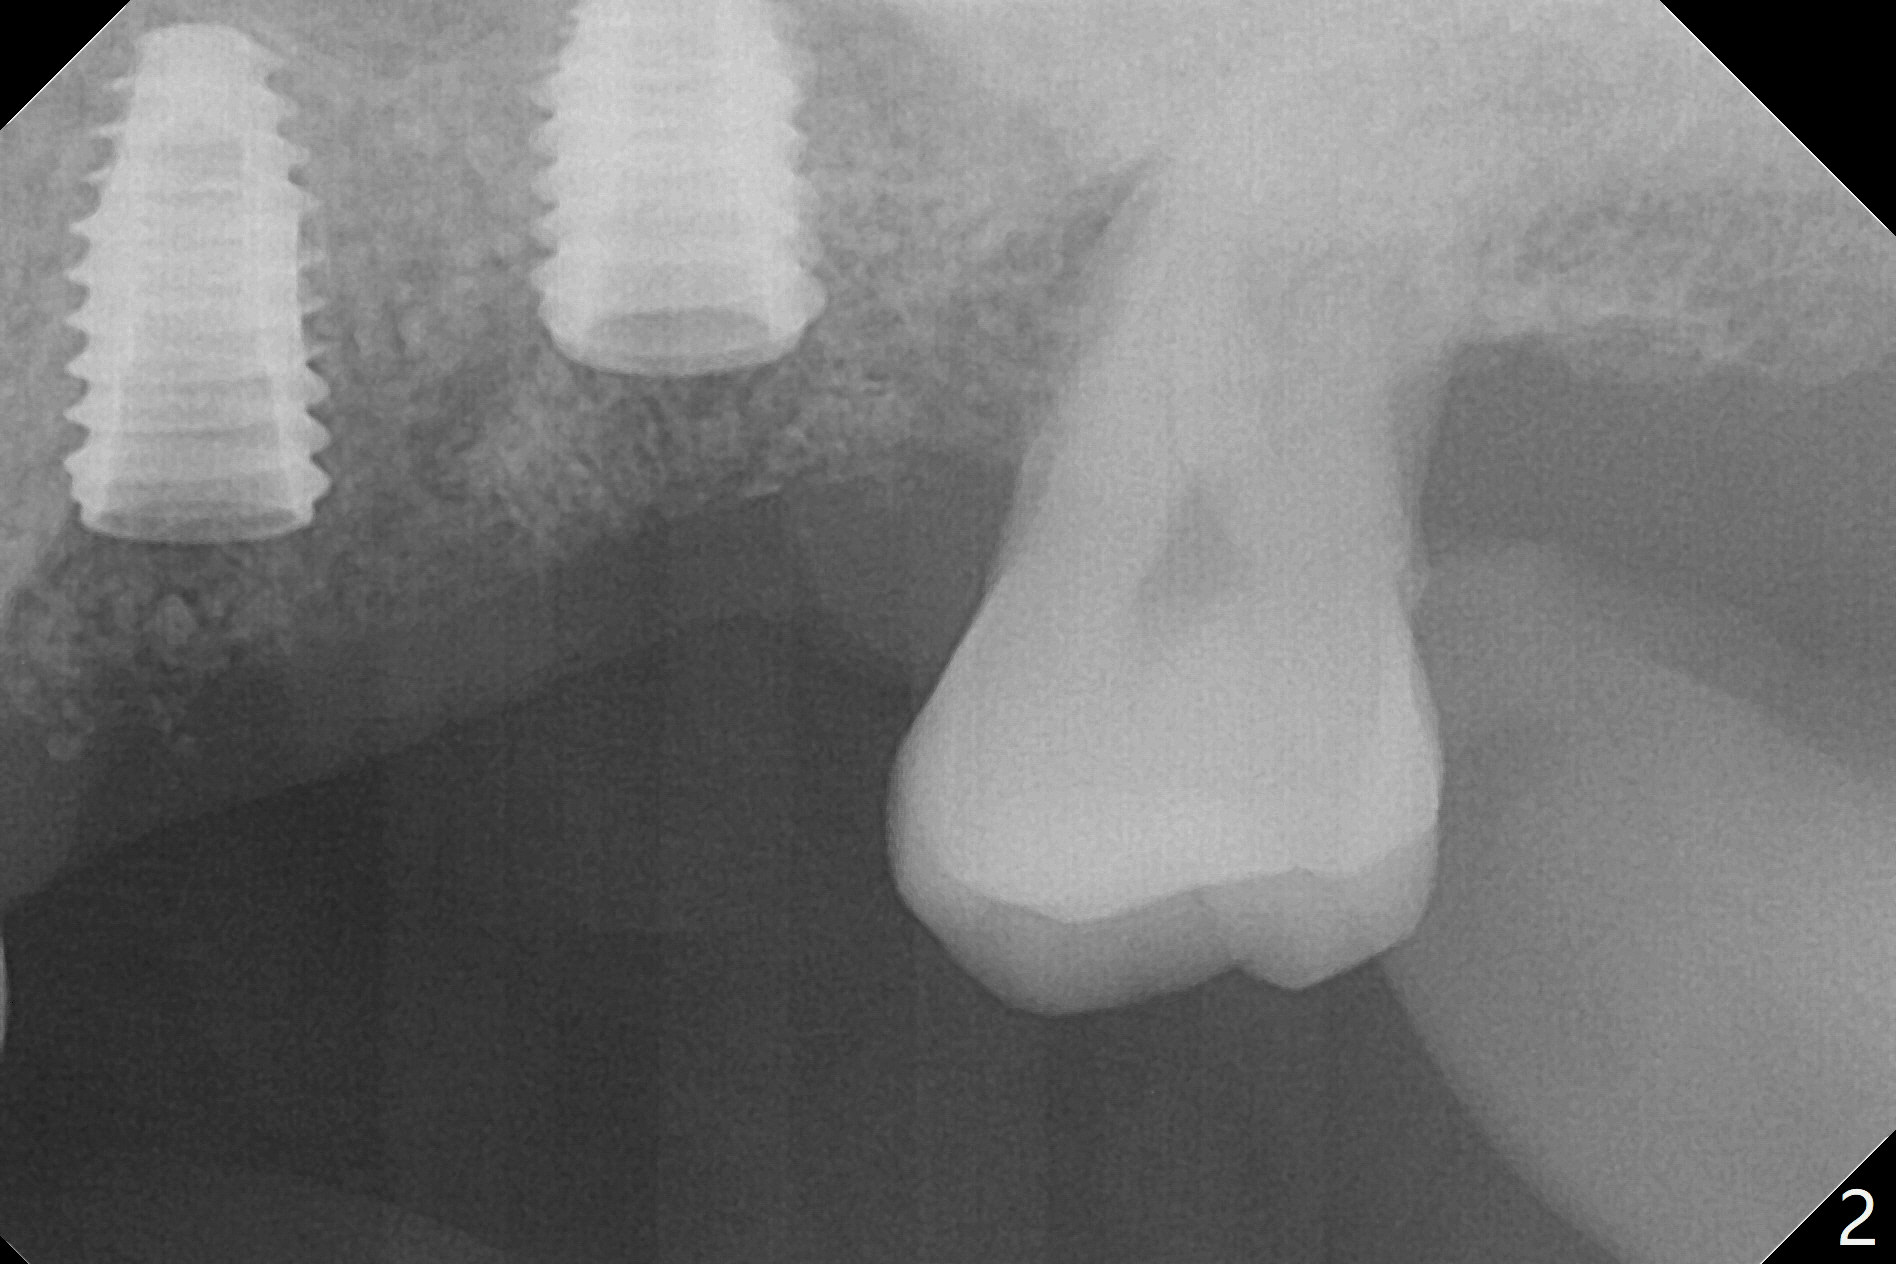

After placement of a 4.5x8.5 mm implant at #13, a vertical anchor pin is used, which is helpful for #14 osteotomy (Fig.1-3). One hand is free. Sinus lift with 2.8 mm reamer is not efficient, since it is difficult to feel stopper. A 5x7.3 mm implant has to be removed from the site of #14 for use of Magic Expanders from 3.0 to 4.3 mm at the depth of 13 mm (gingival level). Autogenous bone harvested from osteotomy is used for sinus lift. It appears that the implants are placed deep; healing abutments with 5 mm cuff are placed (Fig.4 (extraoral bitewing)).